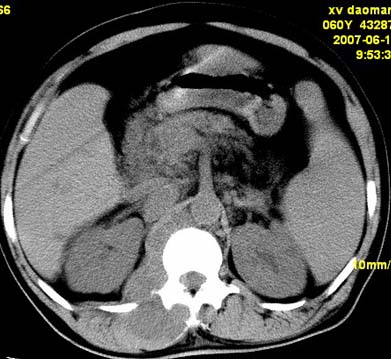

以下是引用还珠格格在2007-6-26 15:05:00的发言:[br]右侧腰大肌、同侧竖脊肌明显肿胀,呈不均匀密度减低影,右肾受压右上前移,脂肪间隙部分消失,另左侧肾盂内可见高密度影,是结石还是造影剂? 不知道病人用造影剂没有?考虑 右侧腰大肌及右侧竖脊肌寒性脓肿形成。[br][br][本贴已被 还珠格格 于 2007-6-26 15:21:35 修改过]

以下是引用小初学者在2007-6-26 15:42:00的发言:[br]1\\右侧腰大肌、同侧竖脊肌脓肿[br]2\\左侧肾盂结石

以下是引用刘明在2007-6-26 16:00:00的发言:[br][br]右侧竖直肌及腰大肌肿胀,脂肪间隙难辨,腹膜后血管旁见多个肿大淋巴结影,椎体附件右侧有压迫吸收、未见硬化迹象,考虑椎旁冷脓肿可能[br]左侧肾盂内可见高密度影,周围有毛刺,本图象是平扫,不是增强,应该是结石[br]